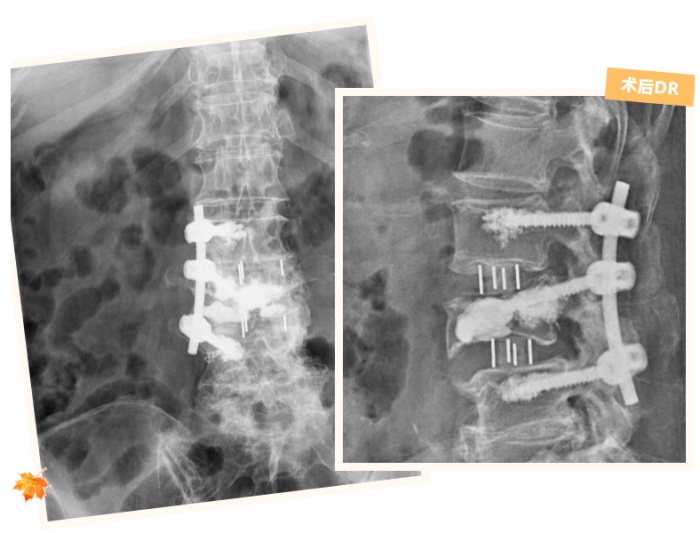

面對這樣的難題,脊柱外科團(tuán)隊沒有急于手術(shù),而是先反復(fù)研究張奶奶的影像檢查結(jié)果,結(jié)合她的癥狀、身體狀況和既往手術(shù)情況,經(jīng)過多次討論,最終制定了一套“精準(zhǔn)拆障、分步修復(fù)”的手術(shù)方案:第一步,通過腰椎間盤摘除術(shù),清除壓迫神經(jīng)的病變椎間盤組織,解決“神經(jīng)受壓”這個核心問題;第二步,采用椎管減壓術(shù)和神經(jīng)根擴(kuò)大減壓術(shù),進(jìn)一步拓寬神經(jīng)通道,徹底解除神經(jīng)受到的擠壓,讓麻木的右腿逐漸恢復(fù)知覺;第三步,實施后外側(cè)入路腰椎椎間植骨融合內(nèi)固定術(shù),在避開骨水泥的“安全區(qū)域”精準(zhǔn)打釘,既能固定彎曲的腰椎,又能重建腰椎的穩(wěn)定性,恢復(fù)腰椎的正常支撐功能。

2.jpg

術(shù)后經(jīng)過一段時間的康復(fù),復(fù)查時張奶奶已經(jīng)能夠獨立行走上百米。她開心地說:“現(xiàn)在腰不酸了,腿也不麻了,終于能像以前一樣正常出門散步了!”